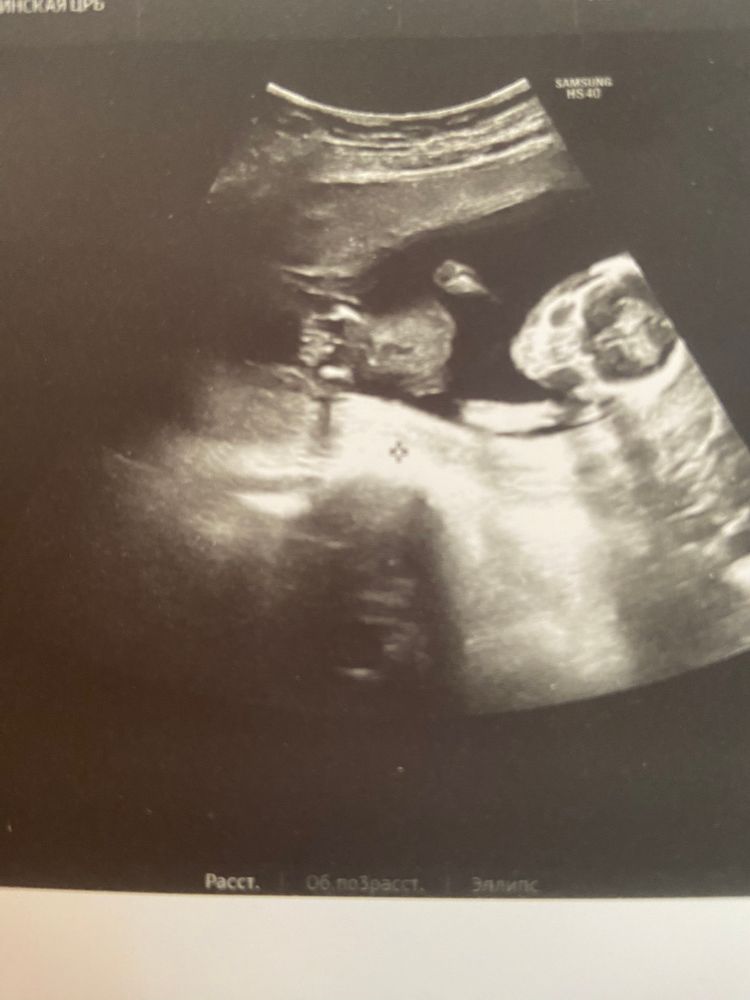

Узи в 16 недель ☺️😍

Девочка вероятно, писюн был бы уже виден

Чашка утреннего кофе, ну вот не знаю 🫠Сказала , что еще не понятно . Я конечно чуть расстроилась , так как хотелось уже узнать ☺️

Дарья, раз малыш активный, может просто не получилось поймать нужный ракурс. Но половые органы в 16 уже точно сформированы. По вашему фото не очень понятно, это вид сверху, получается?

Чашка утреннего кофе, да, сверху )))

Дарья, я не профессионал, да и ракурс не самый удачный, но мне кажется, что девочка.

Я вижу писюн 😁мальчишка)

Анастасия, а я не вижу 😀😀😀мне кажется все гладенько 😂😂

Дарья, вот что я вижу. У девочек не так 😁 Изображение

Анастасия, слушайте ,ну здесь правда на стручок похоже 🙈Но может так получилось ,она сказала ,очень вертлявый малыш .